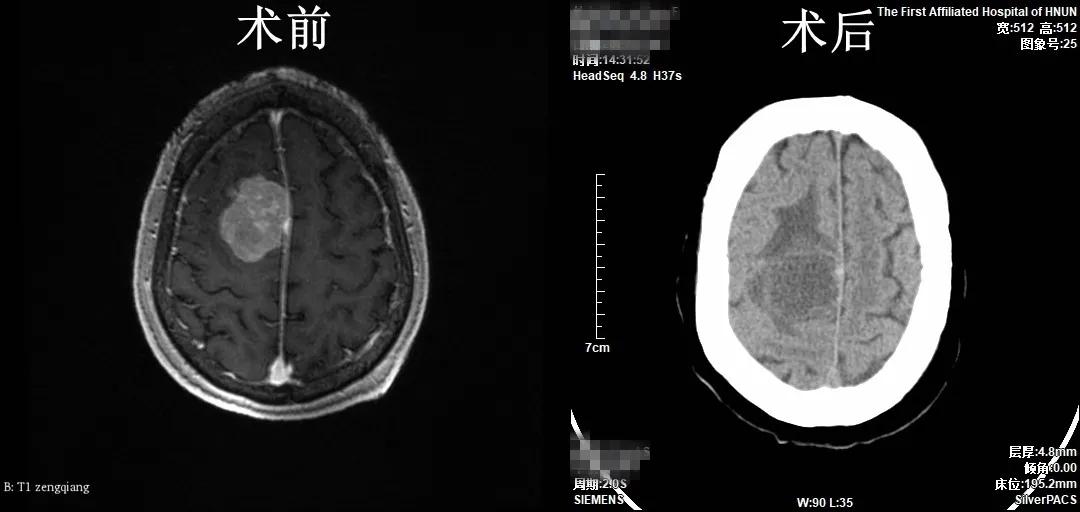

患者武奶奶,82岁,近日出现头痛,间断发作,休息后可缓解,至当地医院行颅脑MRI发现“右侧额叶占位性病变”,为求手术治疗,来我院神经外科就诊。副主任医师张小广接诊患者后,行颅脑增强MRI检查回示“肿瘤位于右侧额叶,大小约42mm×36mm×32mm,与上矢状窦粘连紧密”,手术指征明确,告知家属病情,家属及患者手术愿望强烈。汇报科室副主任马建功,考虑到患者高龄,请麻醉与围术期医学科等相关科室会诊,评估患者手术风险,主治医师王晓斌运用3D-slicer及Sina软件重建患者肿瘤与血管关系三维模型、精确定位肿瘤部位。经充分术前准备及讨论,主任医师方树民带领张小广为患者实施了“显微镜下右额顶开颅矢状窦旁脑膜瘤切除术+颅骨成形术”,手术历时近5小时,手术顺利,完整切除肿瘤。术后病理结果为脑膜瘤。患者恢复顺利,无明显神经功能障碍,痊愈出院。患者及家属对我院神经外科的高超技术及优质服务赞不绝口。